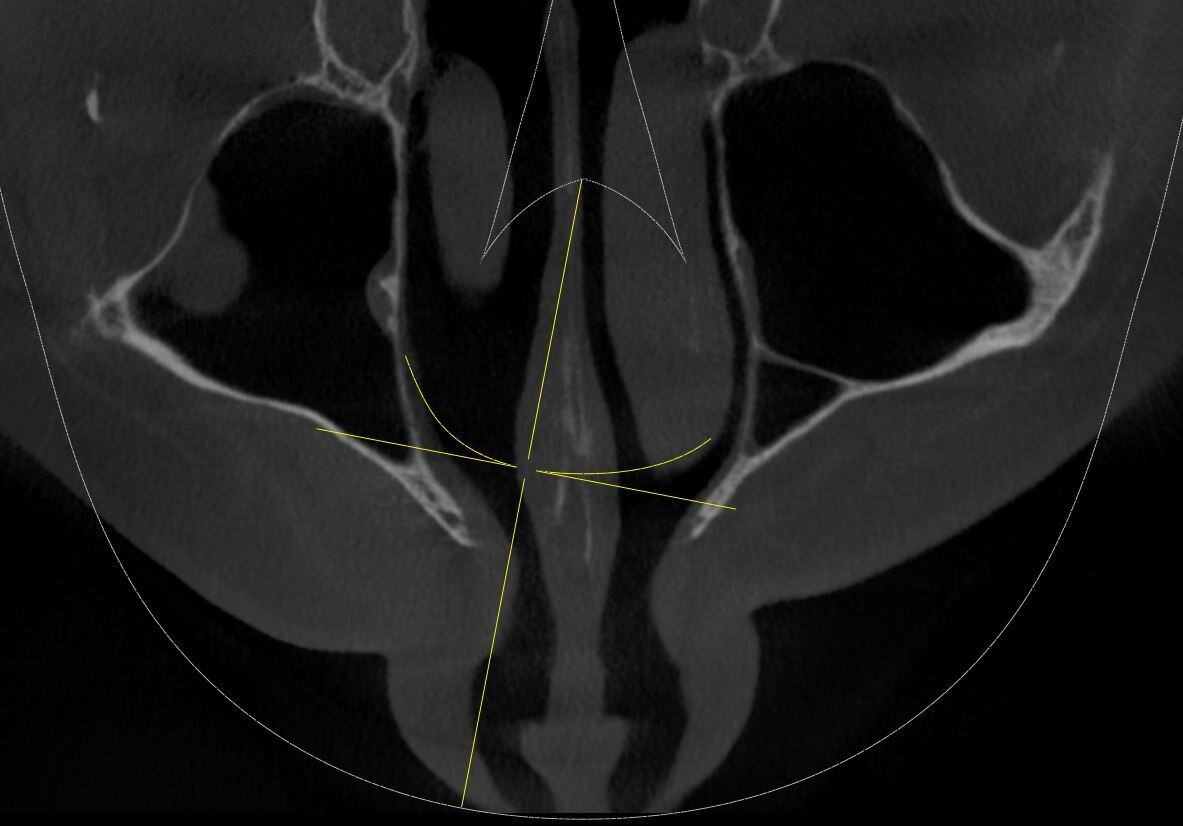

Как стоматологи могут сделать проблему в жизни, даже и не знала что может быть такое. Лечила корни верхнего клыка - обычный пульпит, удалили нерв и запломбировали каналы зубов гуттаперчей. После лечению дня 4 не отходила заморозка. Потом все как-то прошло, через некоторое время у носа образовалась опухоль. Сделали томограмму, оказывается силер или гуттаперча - пломба, чем врач набивает каналы зубов вышел за верхушку корня, и далеко, на томограмме видно что масса вышла за пределы черепа, и застряла в мягких тканях видимо. И эта масса пломбировочного материала - силер вызывает аллергию и опухоль. Верхушка корня - основание корня, его начало. Зуб не болит, не беспокоит, при нажатии ничего не болит, только лицо опухшее и несимметричное. И мой нос и так с перекошенными носовыми перегородками внутри, после того как по нему не хило долбанули, стал еще более неправильной формы (как бы это написать).

Как стоматологи могут сделать проблему в жизни, даже и не знала что может быть такое. Лечила корни верхнего клыка - обычный пульпит, удалили нерв и запломбировали каналы зубов гуттаперчей. После лечению дня 4 не отходила заморозка. Потом все как-то прошло, через некоторое время у носа образовалась опухоль. Сделали томограмму, оказывается силер или гуттаперча - пломба, чем врач набивает каналы зубов вышел за верхушку корня, и далеко, на томограмме видно что масса вышла за пределы черепа, и застряла в мягких тканях видимо. И эта масса пломбировочного материала - силер вызывает аллергию и опухоль.

Верхушка корня - основание корня, его начало. Зуб не болит, не беспокоит, при нажатии ничего не болит, только лицо опухшее и несимметричное.

Почитала, выхождение силера за верхушку корня может провоцировать синуситы, воспаление всех тканей, аллергию, тонзиллит, гайморит простудные заболевания, также воспаление может повредить глазу. Цемент в пазухе - а именно туда может попасть часть пломбы из корня зуба в верхних зубах, продолжительное время может не беспокоить. Однако ряд определенных факторов, включая ослабление иммунных сил, переохлаждение, ОРВИ и даже банальное переутомление, способны активировать воспалительный процесс. Я как раз недавно болела, с температурой 39, лежала несколько дней, чего не было много лет.